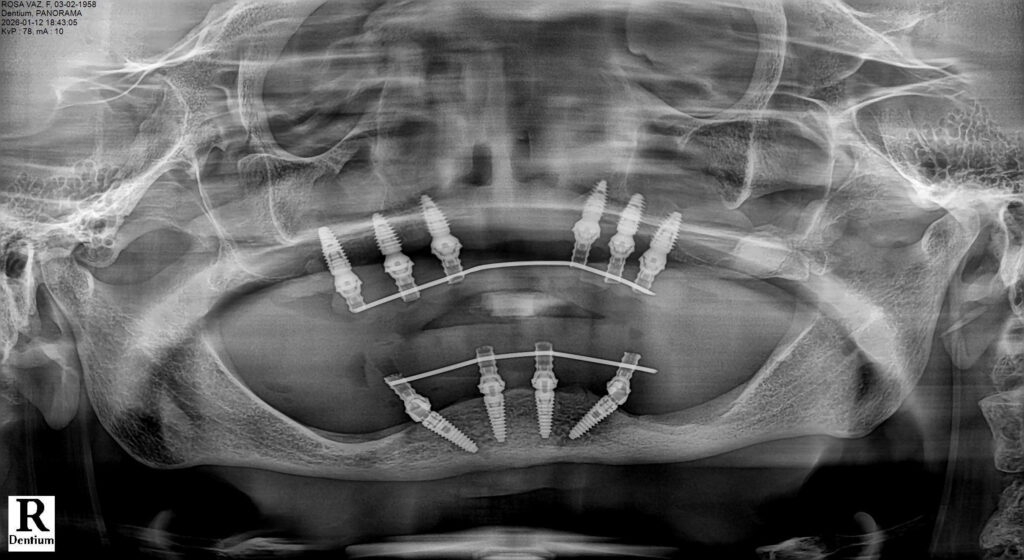

Prosthetic Rehabilitation

The provisional restorations were designed to minimize cantilever forces and provide balanced occlusion. After the osseointegration period, definitive fixed full-arch prostheses were fabricated and delivered.

Outcome and Follow-Up

Postoperative healing was uneventful. Radiographic follow-up demonstrated stable crestal bone levels around all implants. The patient reported significant improvement in comfort, masticatory efficiency, and quality of life.